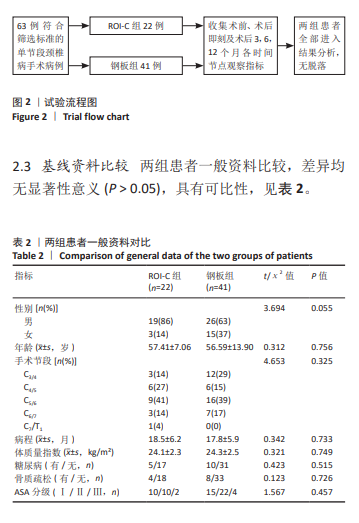

2.6 手术前后影像学评估 两组患者术后C2-7 Cobb角、T1倾斜角,椎间隙高度均较术前显著改善,两组组内不同时间点的C2-7 Cobb角、T1倾斜角,椎间隙高度比较存在显著差异(P < 0.001),而不同分组之间的评分差异无显著性意义(P > 0.05),并且两组在不同时间点的趋势也无显著差异(P > 0.05)。 ROI-C组术后即刻、术后3,6,12个月的C2-7 Cobb角、手术节段椎间隙高度及术后3,6个月的T1倾斜角较术前均显著增加;术后3,6,12个月的C2-7 Cobb角、术后3个月的T1倾斜角均较术后即刻明显增加;术后6个月的C2-7 Cobb角较术后3个月明显增加,差异有显著性意义(P < 0.05)。钢板组术后即刻、术后3,6,12个月的C2-7 Cobb角、手术节段椎间隙高度及术后即刻、术后3,6个月的T1倾斜角均较术前明显增加;与术后即刻相比,钢板组术后3,6,12个月的C2-7 Cobb角及术后3,6个月的T1倾斜角均明显增加;术后6个月的C2-7 Cobb角较术后3个月明显增加,术后12个月的T1倾斜角较术后3个月明显减小;术后12个月的T1倾斜角较术后6个月明显减小,差异有显著性意义(P < 0.05)。见表5。"